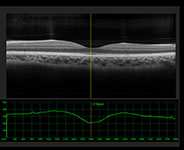

Dilated Retinal Exam